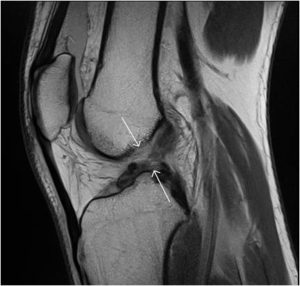

Diagnosis

MRI scan